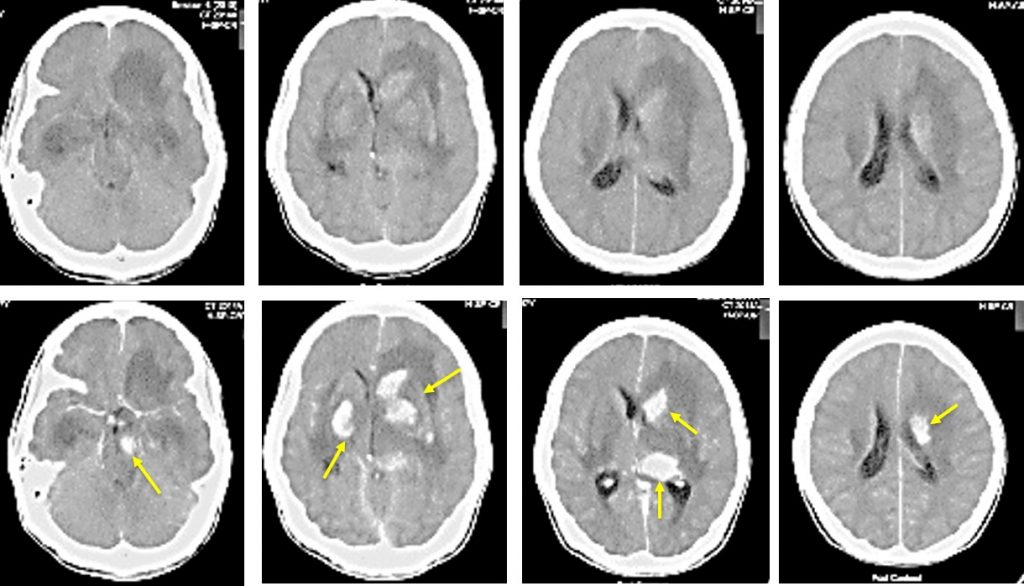

Figure 3 from Various Imaging Manifestations of Posterior Reversible

Pres Ct Scan Lead Encephalopathy Radiology Lead encephalopathy is almost always associated. Lead poisoning affects multiple organs: Encephalopathy is an uncommon but serious presentation of lead toxicity. Lead poisoning is a common occupational health hazard in developing countries. The differential diagnosis of patients presenting with acute encephalopathy is broad. Recognizing the common imaging patterns of toxic and metabolic brain disorders can help radiologists narrow the differential.. Lead Encephalopathy Radiology.

From www.semanticscholar.org

Figure 3 from Various Imaging Manifestations of Posterior Reversible Lead Encephalopathy Radiology Lead poisoning is a common occupational health hazard in developing countries. Lead encephalopathy is almost always associated. Lead poisoning affects multiple organs: The differential diagnosis of patients presenting with acute encephalopathy is broad. Adult hypoglycemic encephalopathy or hypoglycemic brain injury is caused by an imbalance between supply and. Encephalopathy is an uncommon but serious presentation of lead toxicity. Recognizing the. Lead Encephalopathy Radiology.